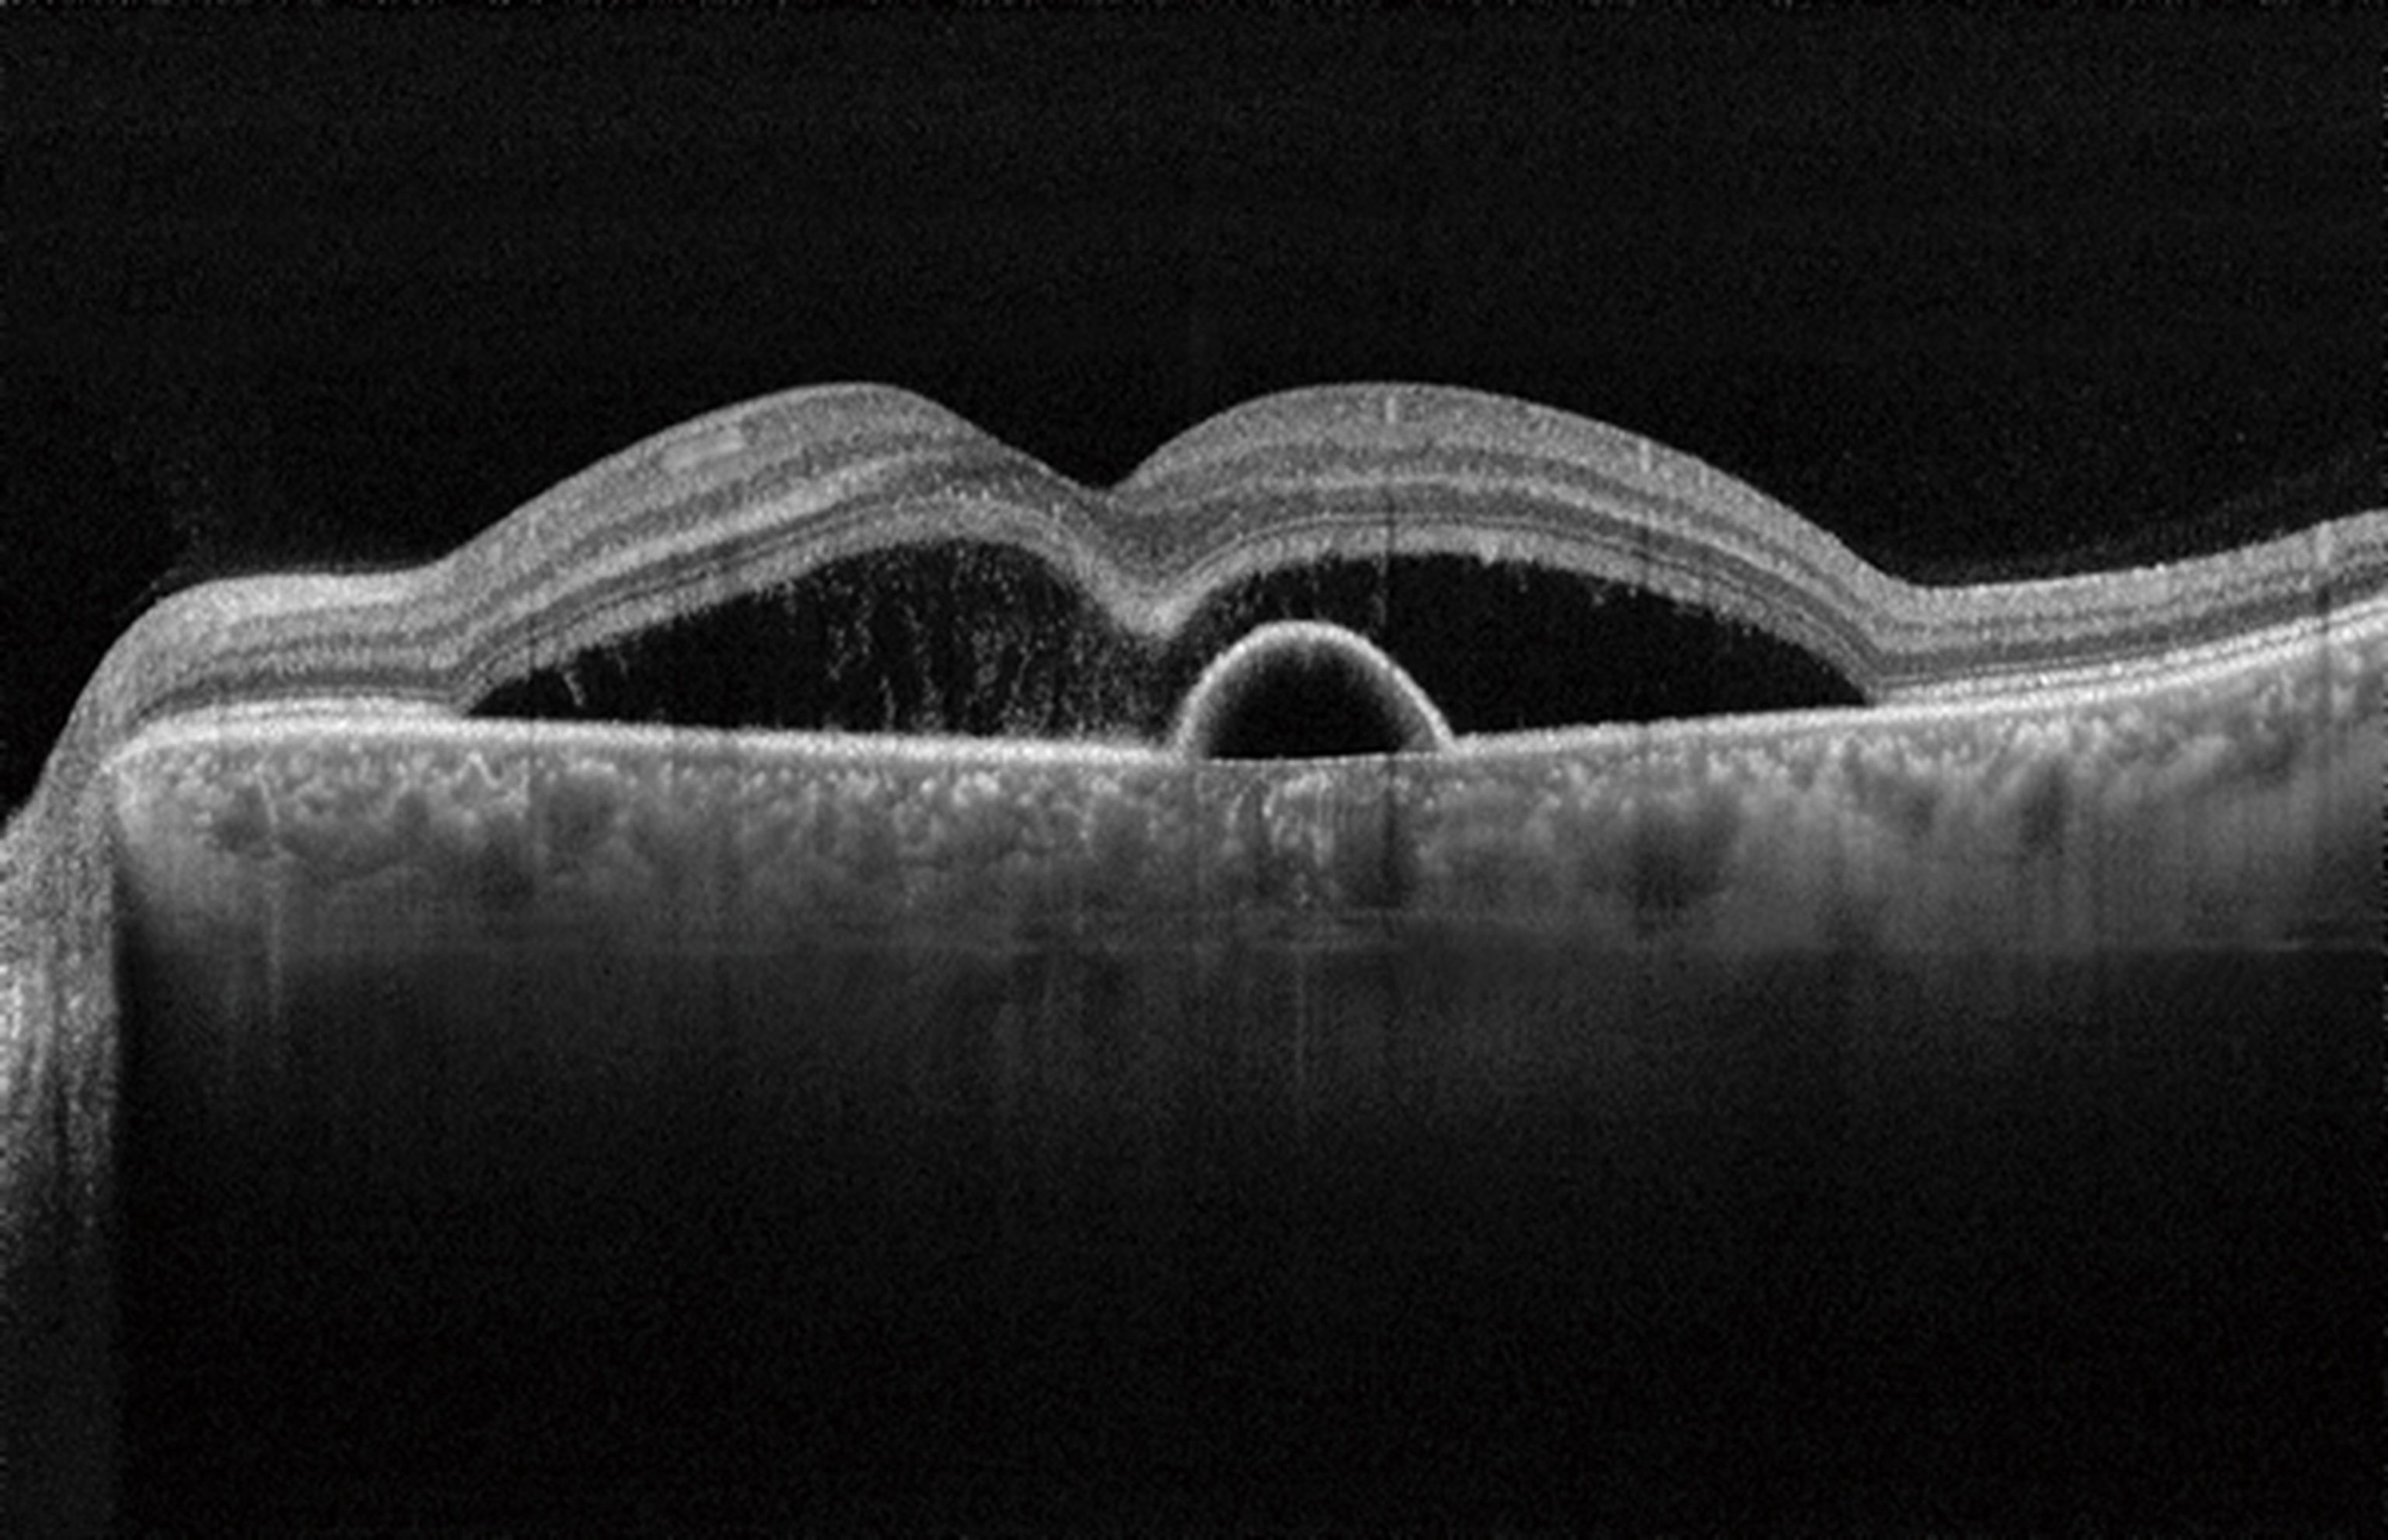

La Corioretinopatia Sierosa Centrale è una patologia insidiosa e subdola della porzione centrale della retina. Coinvolge tipicamente i maschi 30-40 enni e può portare anche a grossi danni permanenti.